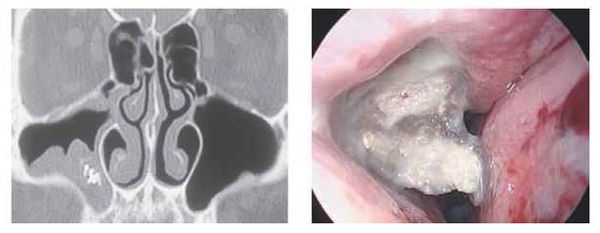

Стандартные рентгенологические методы недостаточно информативны, поскольку они не могут дать объёмную послойную картину черепа, как КТ. На рентгенограммах утолщённая воспалённая слизистая оболочка пазухи имеет серый цвет, участки кальцификатов, которые образуют грибы мицетомы, — белый, а воздух — чёрный. Эти участки характерны только для мицетомы.

Мультиспиральная компьютерная томография остаётся эффективным и единственным способом диагностики мицетомы околоносовой пазухи. Использование трёхмерной реконструкции даёт представление об объёмном взаиморасположении костей, позволяет оценить состояние верхнечелюстной пазухи и зубочелюстной системы (целостность зубов, степень разрушения, цвет, положение в зубном ряду, подвижность, глубину зубодесневых каналов), а при наличии инородных тел точно показывает их форму, размер и местонахождение.

При магнитно-резонансной томографии исследование можно выполнить в двух режимах. С помощью T1-режима в центре поражённой пазухи обычно определяется образование, окружённое слоем жидкости, с низкой интенсивностью сигнала. Такое образование будет тёмным. В режиме T2 МРТ может дать ложноотрицательный результат. При этом режиме грибковое тело имеет низкую интенсивность и выглядит как область, лишённая сигнала, поэтому на снимке может быть принята за воздух.